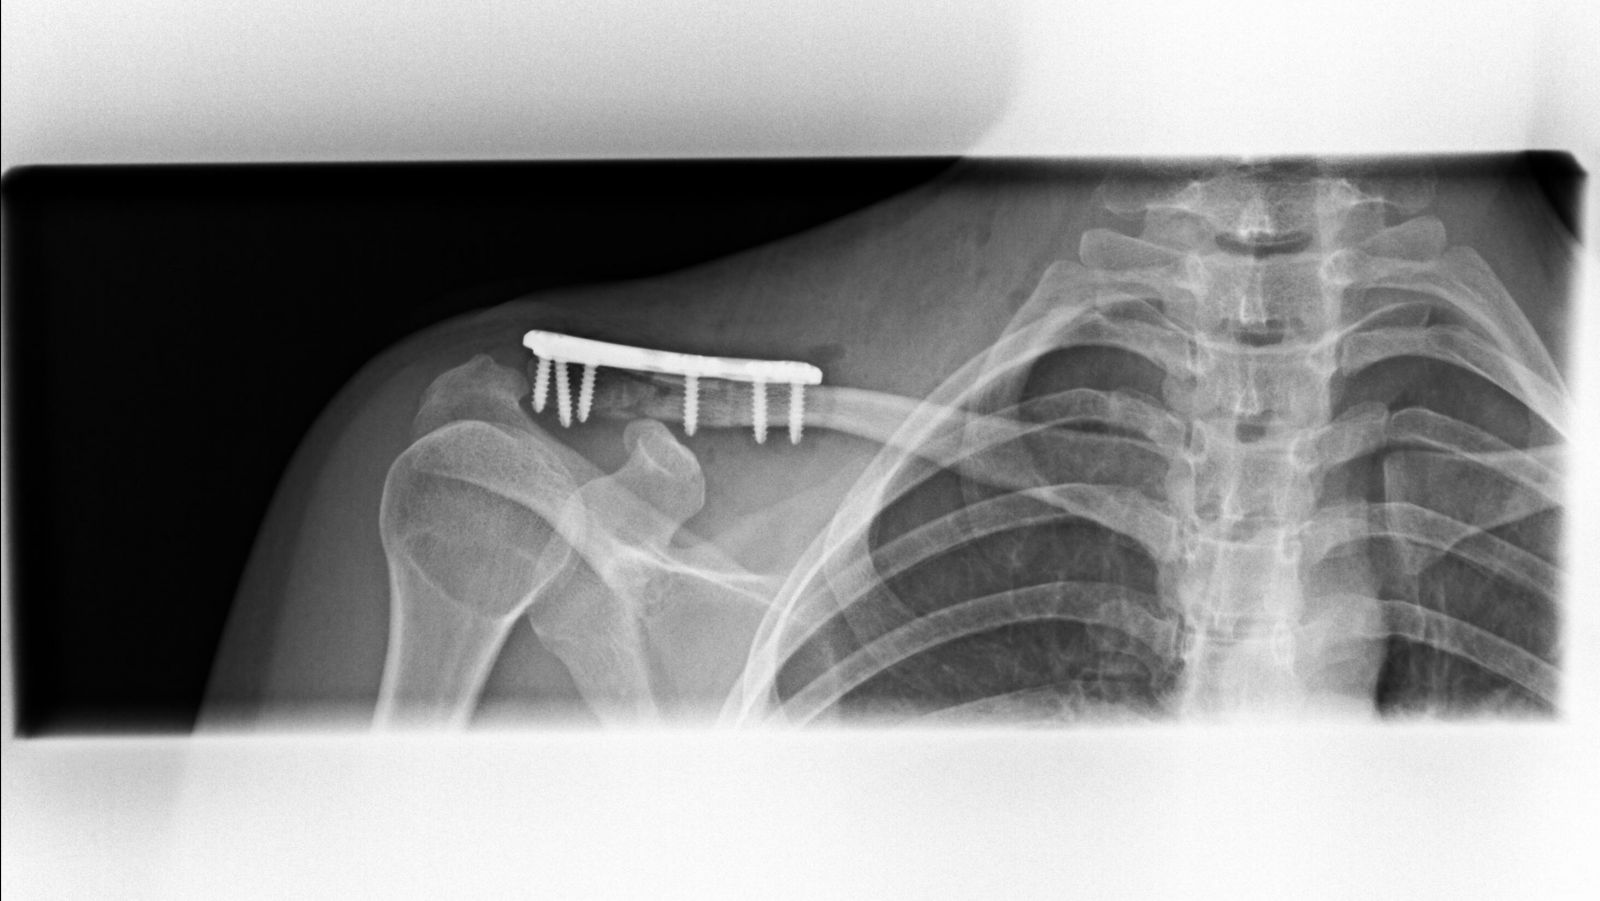

Η οστεοσύνθεση γίνεται κυρίως με χρήση πλάκας και βιδών (κοχλίες). Η πλάκα διαθέτει οπές (τρύπες), μέσα από τις οποίες εισάγουμε τις βίδες στα διάφορα τμήματα της κλείδας και τα συγκρατούμε στην ανατομική τους θέση. Η κατασκευή πλάκα-βίδες-κλείδα είναι πολύ σταθερή και επιτρέπει την πώρωση του κατάγματος σε λίγες εβδομάδες.

Μετεγχειρητικά, οστεοσύνθεση κατάγματος και αποκατάσταση κορακοκλειδικών συνδέσμων